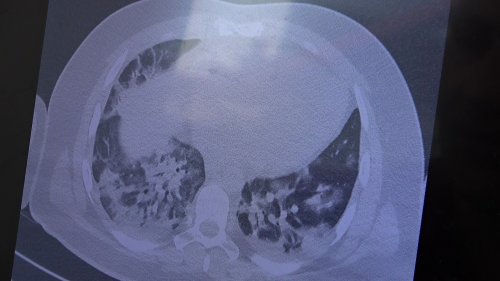

Gençlerin akciğer tomografilerini inceleyen Özkaya, "İki vaka örneği hakkında bilgi vermek istiyorum. İnsanlara bu işin bitmediğini anlatmamız lazım. 30 yaşında aşı olmamış bir hastamızın filminde çok yaygın akciğer hasarı var. Şu an kendisi yoğun bakımda tedavi alıyor. Öte yandan 25 yaşında bir hastamız var. İki doz kovid aşısını da olmamış. Ciddi akciğer tutulumları var. Çok ciddi solunum sıkıntısı ile kovid servisinde yatıyor. Şu an hasta profilimizin büyük bir kısmını bu durum oluşturuyor” ifadelerini kullandı.